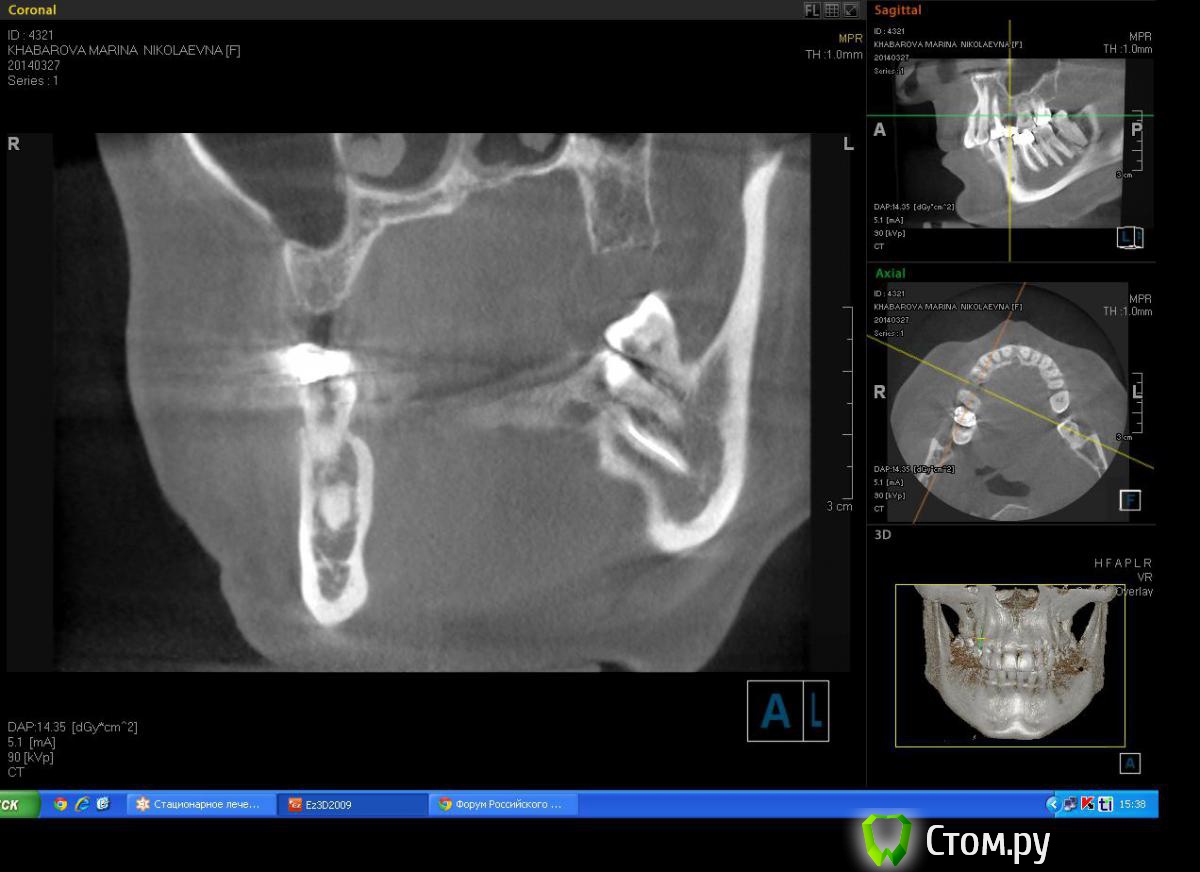

Milanomoda Опубликовано 22 апреля, 2014 Поделиться Опубликовано 22 апреля, 2014 Здравствуйте, уважаемые коллеги. Вообщем обратилась за помощью пациентка - в области 14 зуб, от него консоль на 15, посоветовавшись с ортопедом, приняли решение удалить 14 зуб и одномоментно в лунку имплант, в это же посещение имплантация в области 15. Подскажите пожалуйста с тактикой, можно ли в данном случае рассматривать одномоментную методику имплантации ? Заранаее с пасибо ) Снимки КТ прикладываю. Ссылка на комментарий

Milanomoda Опубликовано 22 апреля, 2014 Автор Поделиться Опубликовано 22 апреля, 2014 Имплантацию в районе 14 зуба планирую ставить в область язычного корня, только вот вопросик такой, при одномоментном протоколе на сколько примерно заглублять нужно будет имплант? Ссылка на комментарий

Milanomoda Опубликовано 22 апреля, 2014 Автор Поделиться Опубликовано 22 апреля, 2014 Картина с планируемым 4.2 х 16 мм имплантом в области 14. Ссылка на комментарий